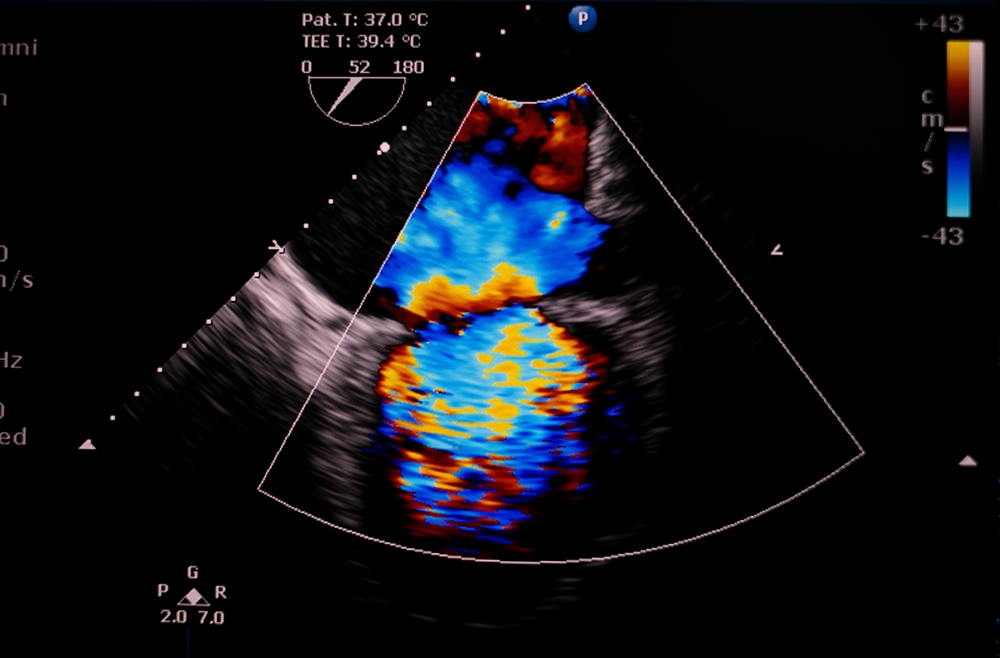

Η κολπική μαρμαρυγή είναι μια παθολογική κατάσταση κατά την οποία η καρδιά χτυπά τελείως ακανόνιστα και άρρυθμα. Πρόκειται για την πλέον συχνή αρρυθμία στον άνθρωπο και διαγιγνώσκεται στο 1%-3% του γενικού πληθυσμού, ενώ το 10% των ατόμων άνω των 80 ετών εμφανίζουν τη νόσο. Περίπου 10 εκατομμύρια άνθρωποι στην Ευρώπη και άνω των 35 εκατομμυρίων παγκοσμίως υποφέρουν από κολπική μαρμαρυγή, ενώ 5 εκατομμύρια νέοι ασθενείς εμφανίζονται ανά έτος. Υπολογίζεται ότι μέχρι το 2060 οι αριθμοί αυτοί θα έχουν διπλασιαστεί. Πρόκειται επομένως για μια σύγχρονη επιδημία, η οποία συσχετίζεται με αυξημένη θνητότητα και νοσηρότητα λόγω προκλήσεως σοβαρών επιπλοκών.